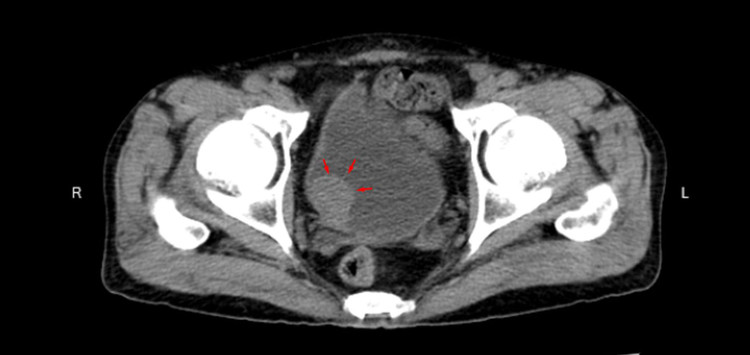

Kết quả chụp cắt lớp vi tính cho thấy: thành bên phải của bàng quang có khối u phát triển đẩy vào lòng bàng quang kích thước 22*24mm.

| Khối u phát triển đẩy vào lòng bàng quang kích thước 22*24mm. Ảnh BVCC |

Bác sĩ chẩn đoán: u bàng quang, tư vấn bệnh nhân làm thêm các dịch vụ cận lâm sàng để loại trừ ung thư bàng quang.